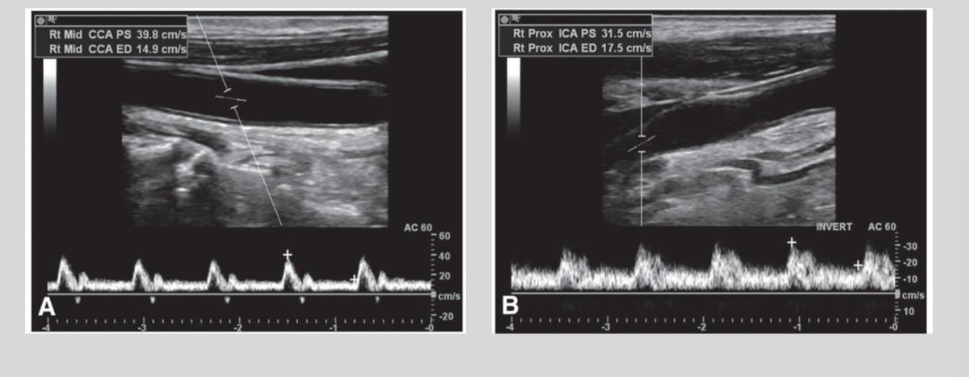

what is this waveform showing?

Bradycardia: slow heartbeat

Tachycardia: rapid heartbeat